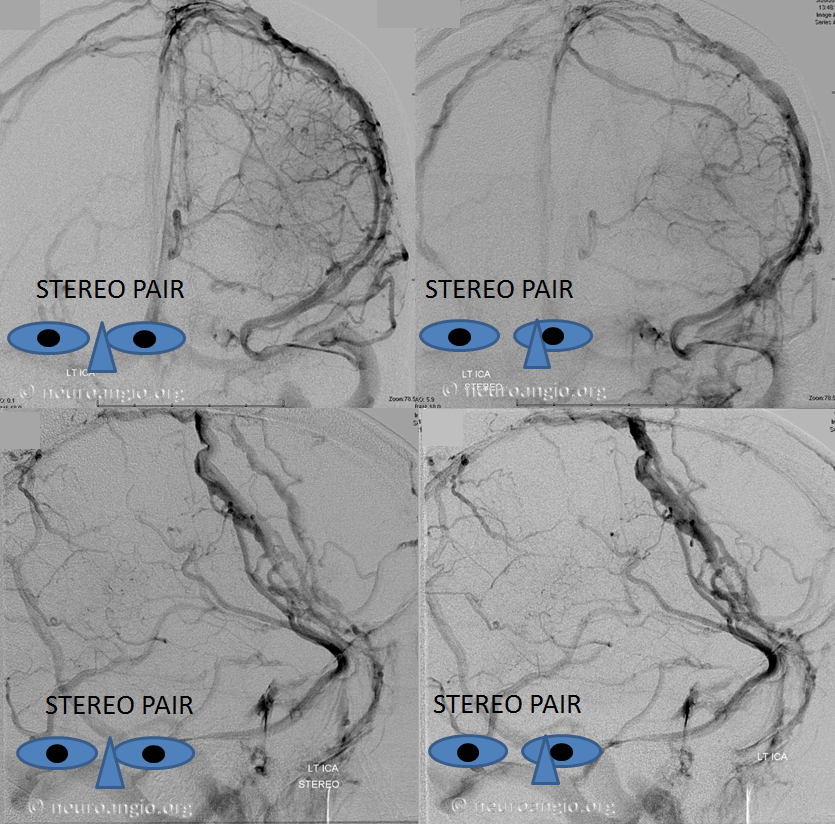

The general neurosurgical fact that the anterior third of the superior sagittal sinus can be safely sacrificed is true almost all the time. When it is not, consequences can be catastrophic. Normally, few veins drain into the anterior 3rd of the SSS, and these usually have collaterals. However, occasionally a large frontal or sylvian vein happens to drain anteriorly. Taking this sinus means risking a venous infarct. Here is an extreme example of dominant inferior left frontal vein draining into the anterior third of the frontal sinus, on MRI. Case courtesy Dr. Howard Riina

Angio is much easier to appreciate. It is well to learn how to spot these veins on MR or CT, as most patients don’t get presurgical angiography for nonvascular lesion

Anaglyph stereo

Stereo of the same

Here is an example of a right parieto-occipital sinus (purple arrows, stereo pair) which collects regional supratentorial and infratentorial veins, emptying into the transverse sinus. Again, this is really only of importance to a surgeon or interventionalist of a procedure in the area is being contemplated.

Same in stereo

Native stereo views

Anaglyph stereo